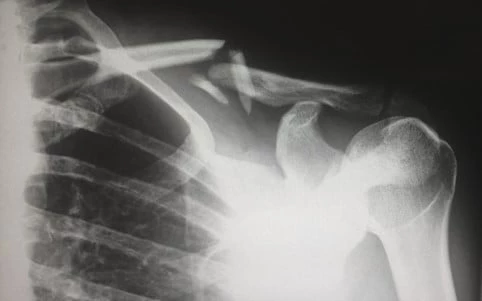

En frossen skulder er en ret sjælden tilstand, som rammer ca. 2 % af befolkningen. Den medicinske betegnelse er ’kapsulit’, og det er en betændelsestilstand i den såkaldte ledkapsel. Ledkapslen er det område af skulderen, som omgiver ledskulderen. Det, som sker ved en frossen skulder, er, at ledkapslens bindevæv skrumper og efter noget tid klistrer sig sammen med ledhovedet. Det er dette, som giver de meget store smerter og den manglende bevægelighed.

Ofte er det faktisk svært at sige, hvad der helt præcist er årsagen til tilstanden, og derfor bliver årsagen kaldt ukendt. Der er dog nogle, som får en lidelsen efter et fald eller en skade på skulderen. Hvis du heller ikke har bevæget skulderen i lang tid – det kan f.eks. være pga. gigt eller et brud – så kan det også resultere i frossen skulder.